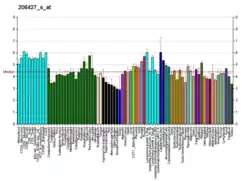

MART-1/melan-A is a protein antigen that is found on the surface of melanocytes. Antibodies against the antigen are used in the medical specialty of anatomic pathology in order to recognize cells of melanocytic differentiation, useful for the diagnosis of a melanoma. The same name is also used to refer to the gene which codes for the antigen.

The MART-1/melan-A antigen is specific for the melanocyte lineage, found in normal skin, the retina, and melanocytes, but not in other normal tissues. It is thus useful as a marker for melanocytic tumors (melanomas) with the caveat that it is normally found in benign nevi as well.